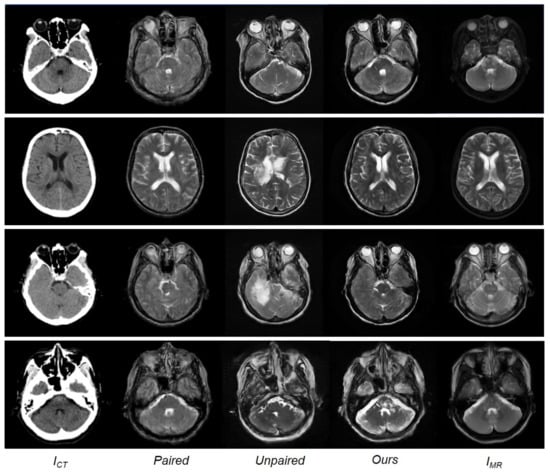

Although having trained with limited paired data, the model using the paired training data is observed to outperform the CycleGAN model using the unpaired data. Table 1 indicates that the approach adopted in this study, i.e., training with paired and unpaired data together, exhibited the best performance across all measurements, with the lowest MAE and highest PSNR and SSIM values compared to the conventional paired and unpaired training methods. Figure 6 shows a qualitative comparison between the paired training, unpaired training, and the approach presented herein. The results of the training with paired data appeared reasonable but generated blurry outputs. The images obtained with unpaired training were realistic but lost anatomical information in areas of soft brain tissue and contained artifacts in areas with bony structures. The method presented herein learns estimation using paired and unpaired data. While the quality of the results closely approximates the reference MR images, for some details, the results obtained are observed to be much clearer than the reference MR images.

Figure 6. From (left) to (right): Input CT image, synthesized MR image with paired training, synthesized MR image with unpaired training, synthesized MR images with paired and unpaired training (ours), and the reference MR images.